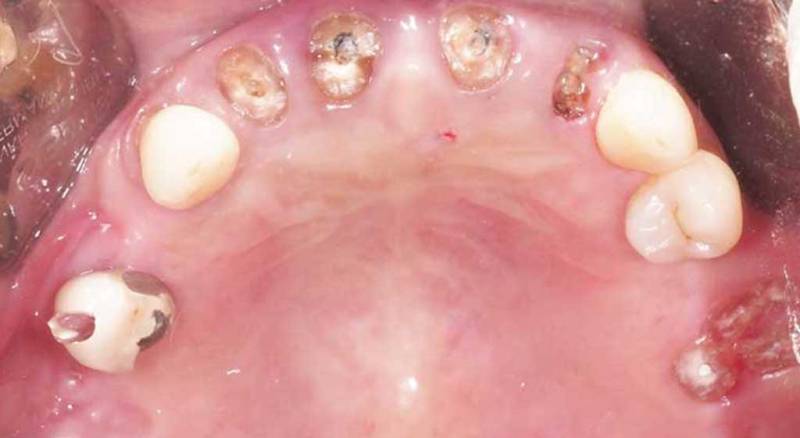

窩洞保存術術前

窩洞保存術術後